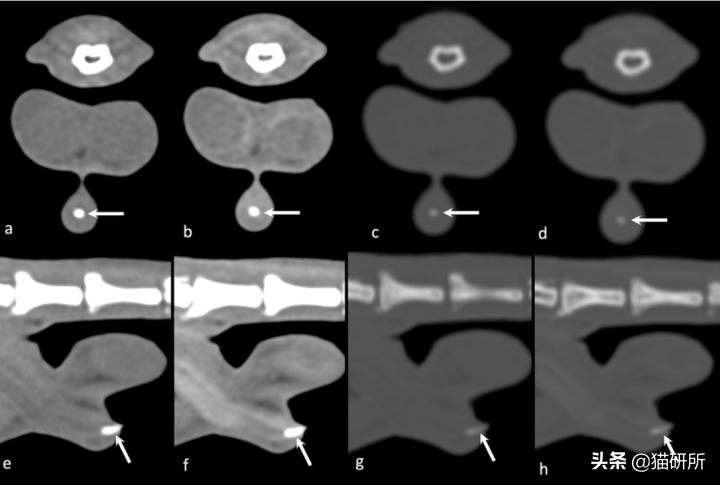

猫咪的阴茎骨(箭头处)是软骨(CT前2、后2分别是软组织、骨骼算法)图自:引文3

[3] Mauricio, Tobón, Restrepo, et al. CT characterisation of the feline os penis.[J]. Journal of feline medicine and surgery, 2019:1098612X19873195.